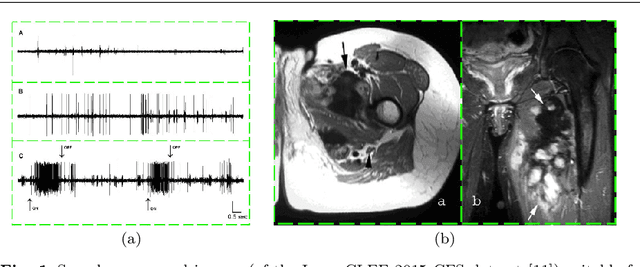

Abstract:Content-based analysis and retrieval of digital images found in scientific articles is often hindered by images consisting of multiple subfigures (compound figures). We address this problem by proposing a method to automatically classify and separate compound figures, which consists of two main steps: (i) a supervised compound figure classifier (CFC) discriminates between compound and non-compound figures using task-specific image features; and (ii) an image processing algorithm is applied to predicted compound images to perform compound figure separation (CFS). Our CFC approach is shown to achieve state-of-the-art classification performance on a published dataset. Our CFS algorithm shows superior separation accuracy on two different datasets compared to other known automatic approaches. Finally, we propose a method to evaluate the effectiveness of the CFC-CFS process chain and use it to optimize the misclassification loss of CFC for maximal effectiveness in the process chain.